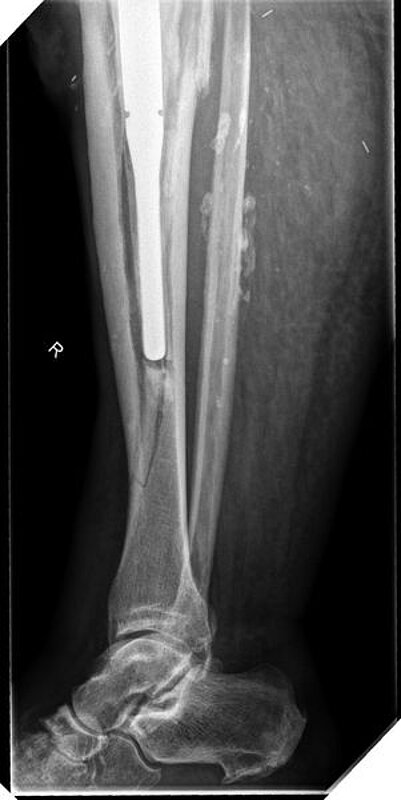

Im weiteren Verlauf zeigten sich die Weichteile des rechten Unterschenkels zunehmend mazeriert und belegt. Zudem sei der Patient erneut gestürzt. Eine erneut durchgeführte Röntgendiagnostik zeigte erneut eine periprothetische Tibiafraktur (Abbildung 3) bei einliegender achsgeführter KTP mit langem tibialem Stem und bekanntem periprothetischem Infekt mit Candida parapsilosis. Wir haben die Befunde ausführlich mit dem Patienten besprochen und in Zusammenschau der Befunde schließlich die Indikation zur Oberschenkelamputation gestellt.

Diese konnte komplikationslos im Mai 2018 durchgeführt werden (Abbildung 4 und 5).

Womöglich hätte der drastische Schritt einer Amputation durch eine frühzeitige Prothesensanierung, welche jedoch durch den Patienten abgelehnt wurde, verhindert werden können.